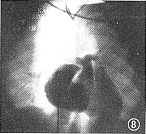

右心房造影:右房耳部和体部均增大,右心房显影后随即左心房隐约显影(提示房间有右向左分流)(图8);4例右室电影造影:显示右室收缩和舒张功能欠佳;3例左心室增大,未见室间交通。

图8 右心房造影正位:右心房增大,左房隐约显影(提示有房间隔交通)